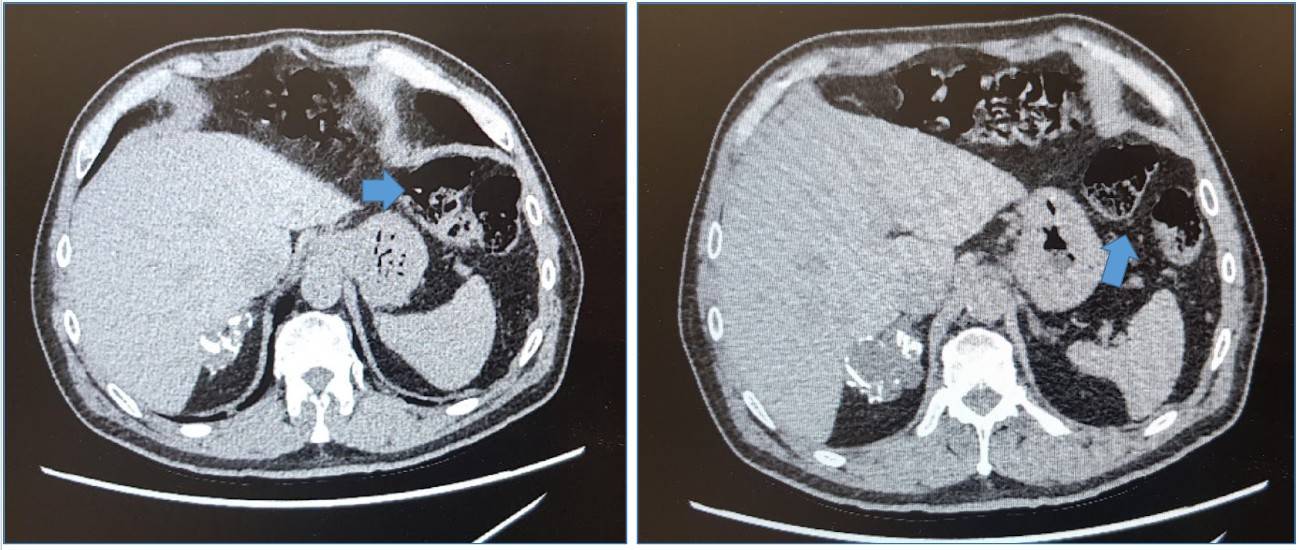

En la Exploración física sin datos anormales, le realizan TAC de abdomen con el hallazgo que se observa en las imágenes, se decide resecar dicha lesión.

Corte tomográfico abdominal